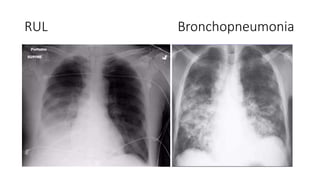

RUL RML

RUL Bronchopneumonia